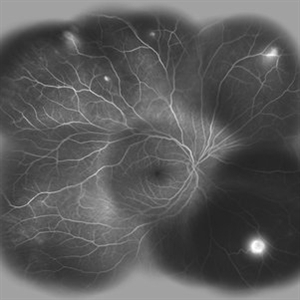

Behcet's Disease Behcet's DiseaseMar 13 2013 by Hamid Ahmadieh, MD Wide field FA of the right eye of a 23-year-old man with retinal vasculitis and branch retinal vein occlusion (BRVO) due to Behcet's disease . Photographer: Solmaz Shahmohammad, Negah Eye Center, Tehran Imaging device: Heidelberg Spectralis Condition/keywords: branch retinal vein occlusion (BRVO), retinal vasculitis